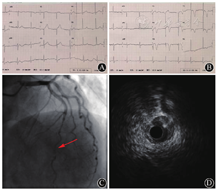

患者女性,53岁,因"胸痛2 h"入院。患者于入院前2 h无诱因突发胸骨后疼痛,向左上肢放射,持续不缓解,急诊入院。既往否认高血压病、糖尿病、结缔组织病等。否认烟酒嗜好。体格检查:血压188/105 mmHg,心率70次/min,神志清楚,双肺呼吸音清,未闻及干湿性啰音。心律齐,各瓣膜区未闻及杂音,腹软,双下肢无水肿。心电图提示前壁导联ST段上抬伴T波高尖(图1A)。超声心动图提示:前间隔、左室前壁中间段及心尖段运动幅度减低,左室射血分数为45%。诊断为:急性前壁ST段抬高型心肌梗死。立即予拜阿司匹林300 mg、替格瑞洛180 mg口服。急诊冠状动脉造影,见前降支中远段管腔严重狭窄,病变呈弥漫、偏心性表现,左主干、回旋支及右冠状动脉均未见异常(图1C)。进一步行血管内超声(intravascular ultrasound,IVUS)可见前降支全程内膜完整,中远段12~4点钟方向范围内可见明显壁内血肿压迫、管腔重度狭窄,血肿段未见与血管管腔的交通口,病变段未见粥样硬化斑块,考虑为冠状动脉自发夹层(图1D)。未行支架植入,结束手术。术后按ST段抬高型心肌梗死给予"拜阿司匹林、替格瑞洛、低分子肝素、瑞舒伐他汀、美托洛尔"等药物治疗。住院期间患者未再发胸痛,动态监测超敏肌钙蛋白I水平达峰值4.13 ng/ml后下降(正常参考值0~0.03 ng/ml),于出院前降至正常范围内。复查心电图提示前壁导联ST段回落伴T波倒置(图1B),康复出院。

A:急诊心电图提示前壁导联ST段抬高;B:术后心电图提示ST段回落,T波倒置;C:急诊造影提示前降支中远段弥漫狭窄(箭头所指);D:血管内超声见冠状动脉壁内血肿(箭头所指)